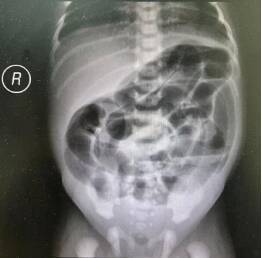

术前X片显示低位肠梗阻